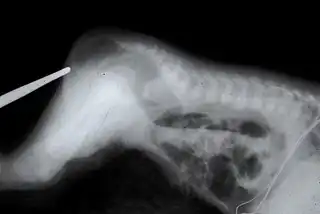

Ano imperforado

El ano imperforado (también, atresia anal, atresia rectal o atresia anorrectal) es una enfermedad congénita que se caracteriza porque el recto no está conectado al ano. Ocurre en 1 de cada 5000 nacidos vivos. La causa de este defecto del nacimiento es desconocida. Este problema es factible de solucionar mediante una intervención quirúrgica.[13]